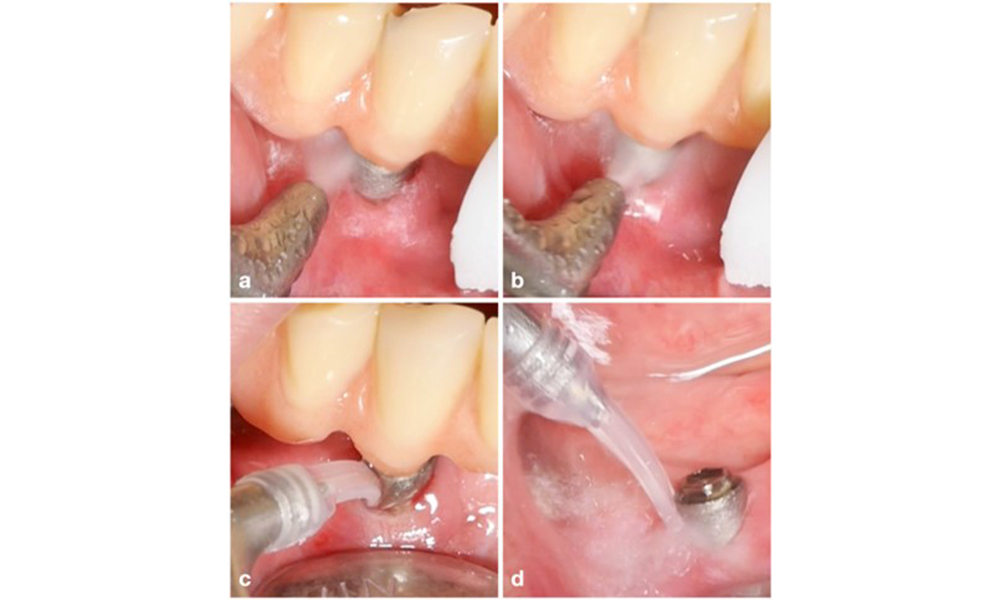

Die Wahl der Mittel hängt von den klinischen Gegebenheiten wie zum Beispiel Zahnstein im Unterschied zu weichen Belägen ab. Bei Zahnstein sollten als Erstes Titan- bzw. Kunststoffküretten oder Ultraschallscaler mit speziell geformter Spitze zum Einsatz kommen, gefolgt von einem Luftpoliergerät (Abb. 7). Bei ausschließlich weichen Belägen ist ein Luftpoliergerät allein unter Umständen ausreichend. Luftpoliergeräte sind bediener- und patientenfreundlich und mindestens so wirksam wie Standardinstrumente (Schwarz et al. 2015a).

Das Management einer Periimplantitis bei als therapierbar eingestuften Implantaten besteht aus einer nicht-chirurgischen Phase, oftmals gefolgt von einer chirurgischen Intervention. Bei den nicht-chirurgischen Verfahren kommen ähnliche Maßnahmen zum Einsatz wie bei der Behandlung einer periimplantären Mukositis. Laborexperimente lassen darauf schließen, dass Luftpoliergeräte mit subgingivaler Düse bei der Biofilmentfernung im Vergleich zu Hand- oder Ultraschallinstrumenten allem Anschein nach bestimmte Vorteile bieten (Herrera et al. 2023; Moharrami et al. 2019; Ronay et al. 2017) (Abb. 9).